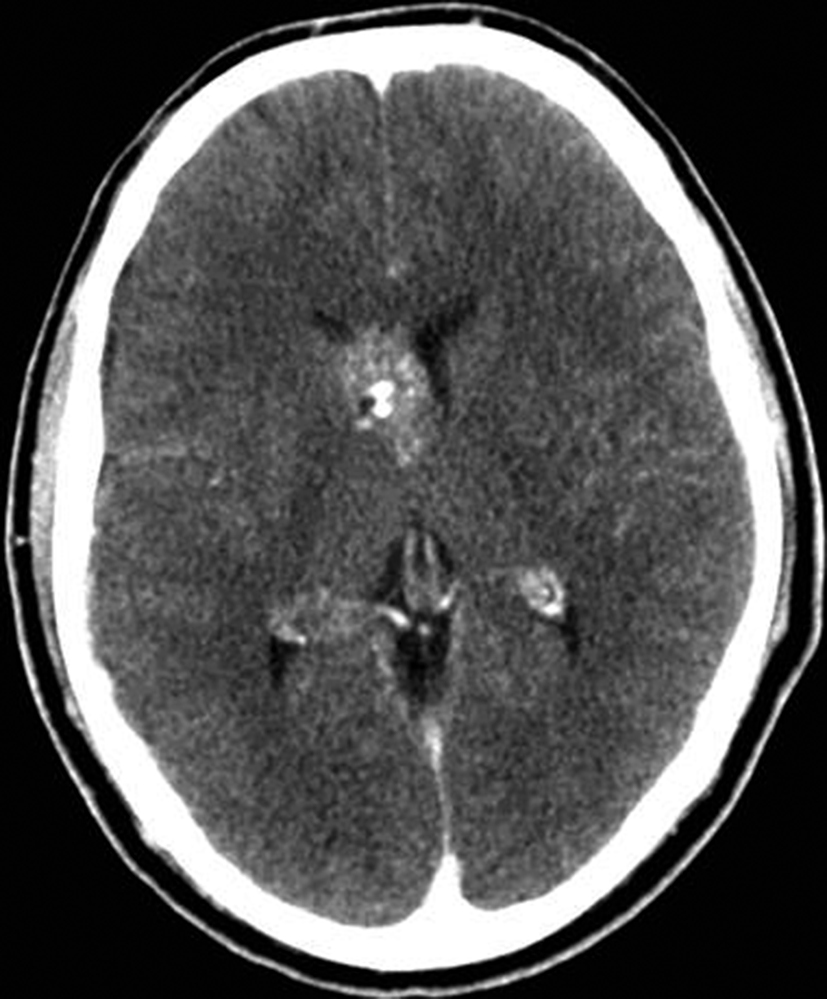

Se presenta el caso clínico de un paciente de sexo masculino, de 36 años de edad, sin antecedentes personales a destacar. Consulta por cefalea holocraneana de larga data, sin déficit neurológico y examen físico normal. Dada la clínica del paciente se realiza una tomografía computada de cráneo sin contraste intravenoso que identifica una lesión bien definida espontáneamente hiperdensa, heterogénea con calcificaciones puntiformes localizada en el asta frontal del ventrículo lateral derecho. No hay edema peri-lesional, efecto de masa ni hidrocefalia (Figura 1- A). Debido a los hallazgos se decide administrar contraste intravenoso, no evidenciándose realce significativo de la lesión (Figura 1- B).

Se efectúa un control imagenológico al año del diagnóstico mediante una TC sin y con contraste (Figura 5 – A y B), donde se evidencia la lesión sin cambios significativos en cuanto a su tamaño y características.

a) TC sin contraste. Lesión intraventricular hiperdensa, heterogénea con pequeñas calcificaciones.

a) TC con contraste. No se identifica realce significativo de la lesión.

Figura 5

a y b) Cortes axiales de TC sin y con contraste intravenoso. Control tomográfico al año del estudio inicial, no se observan cambios significativos de la lesión.